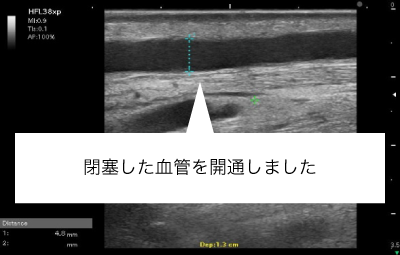

シャント閉塞はしなくても、血流がほとんどないシャント血管部分を長期間放置すると血管内が線維化し部分的に血管が閉塞することがあります。10cm未満のCTOであれば、閉塞した血管の血流を再開させることも可能です。これにより、穿刺部位を広げることが可能となります。